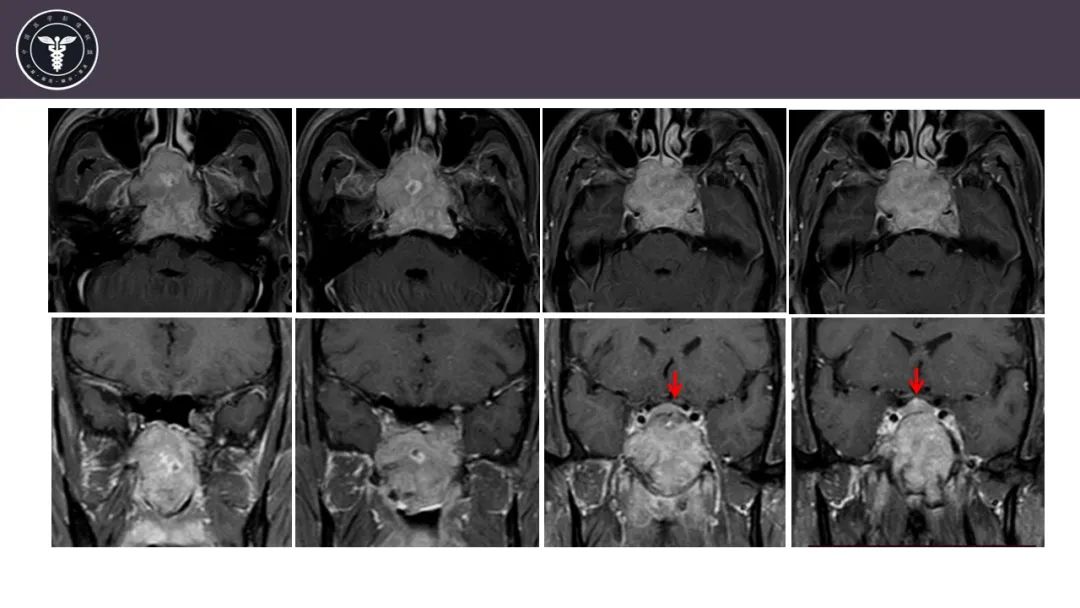

病例1

【病例】斜坡区骨巨细胞瘤 VS 脊索瘤-2